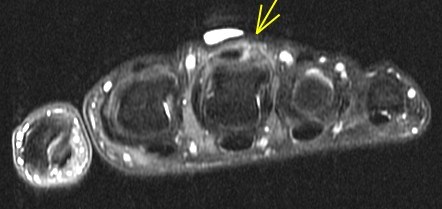

33 yo with 3rd MCP pain. Patient is a boxer. Rule out (in) Boxers knuckle

Longitudinal tear of the ulnar sagittal band of the 3rd MCP = Boxers knuckle. Reference article.

Boxers knuckle